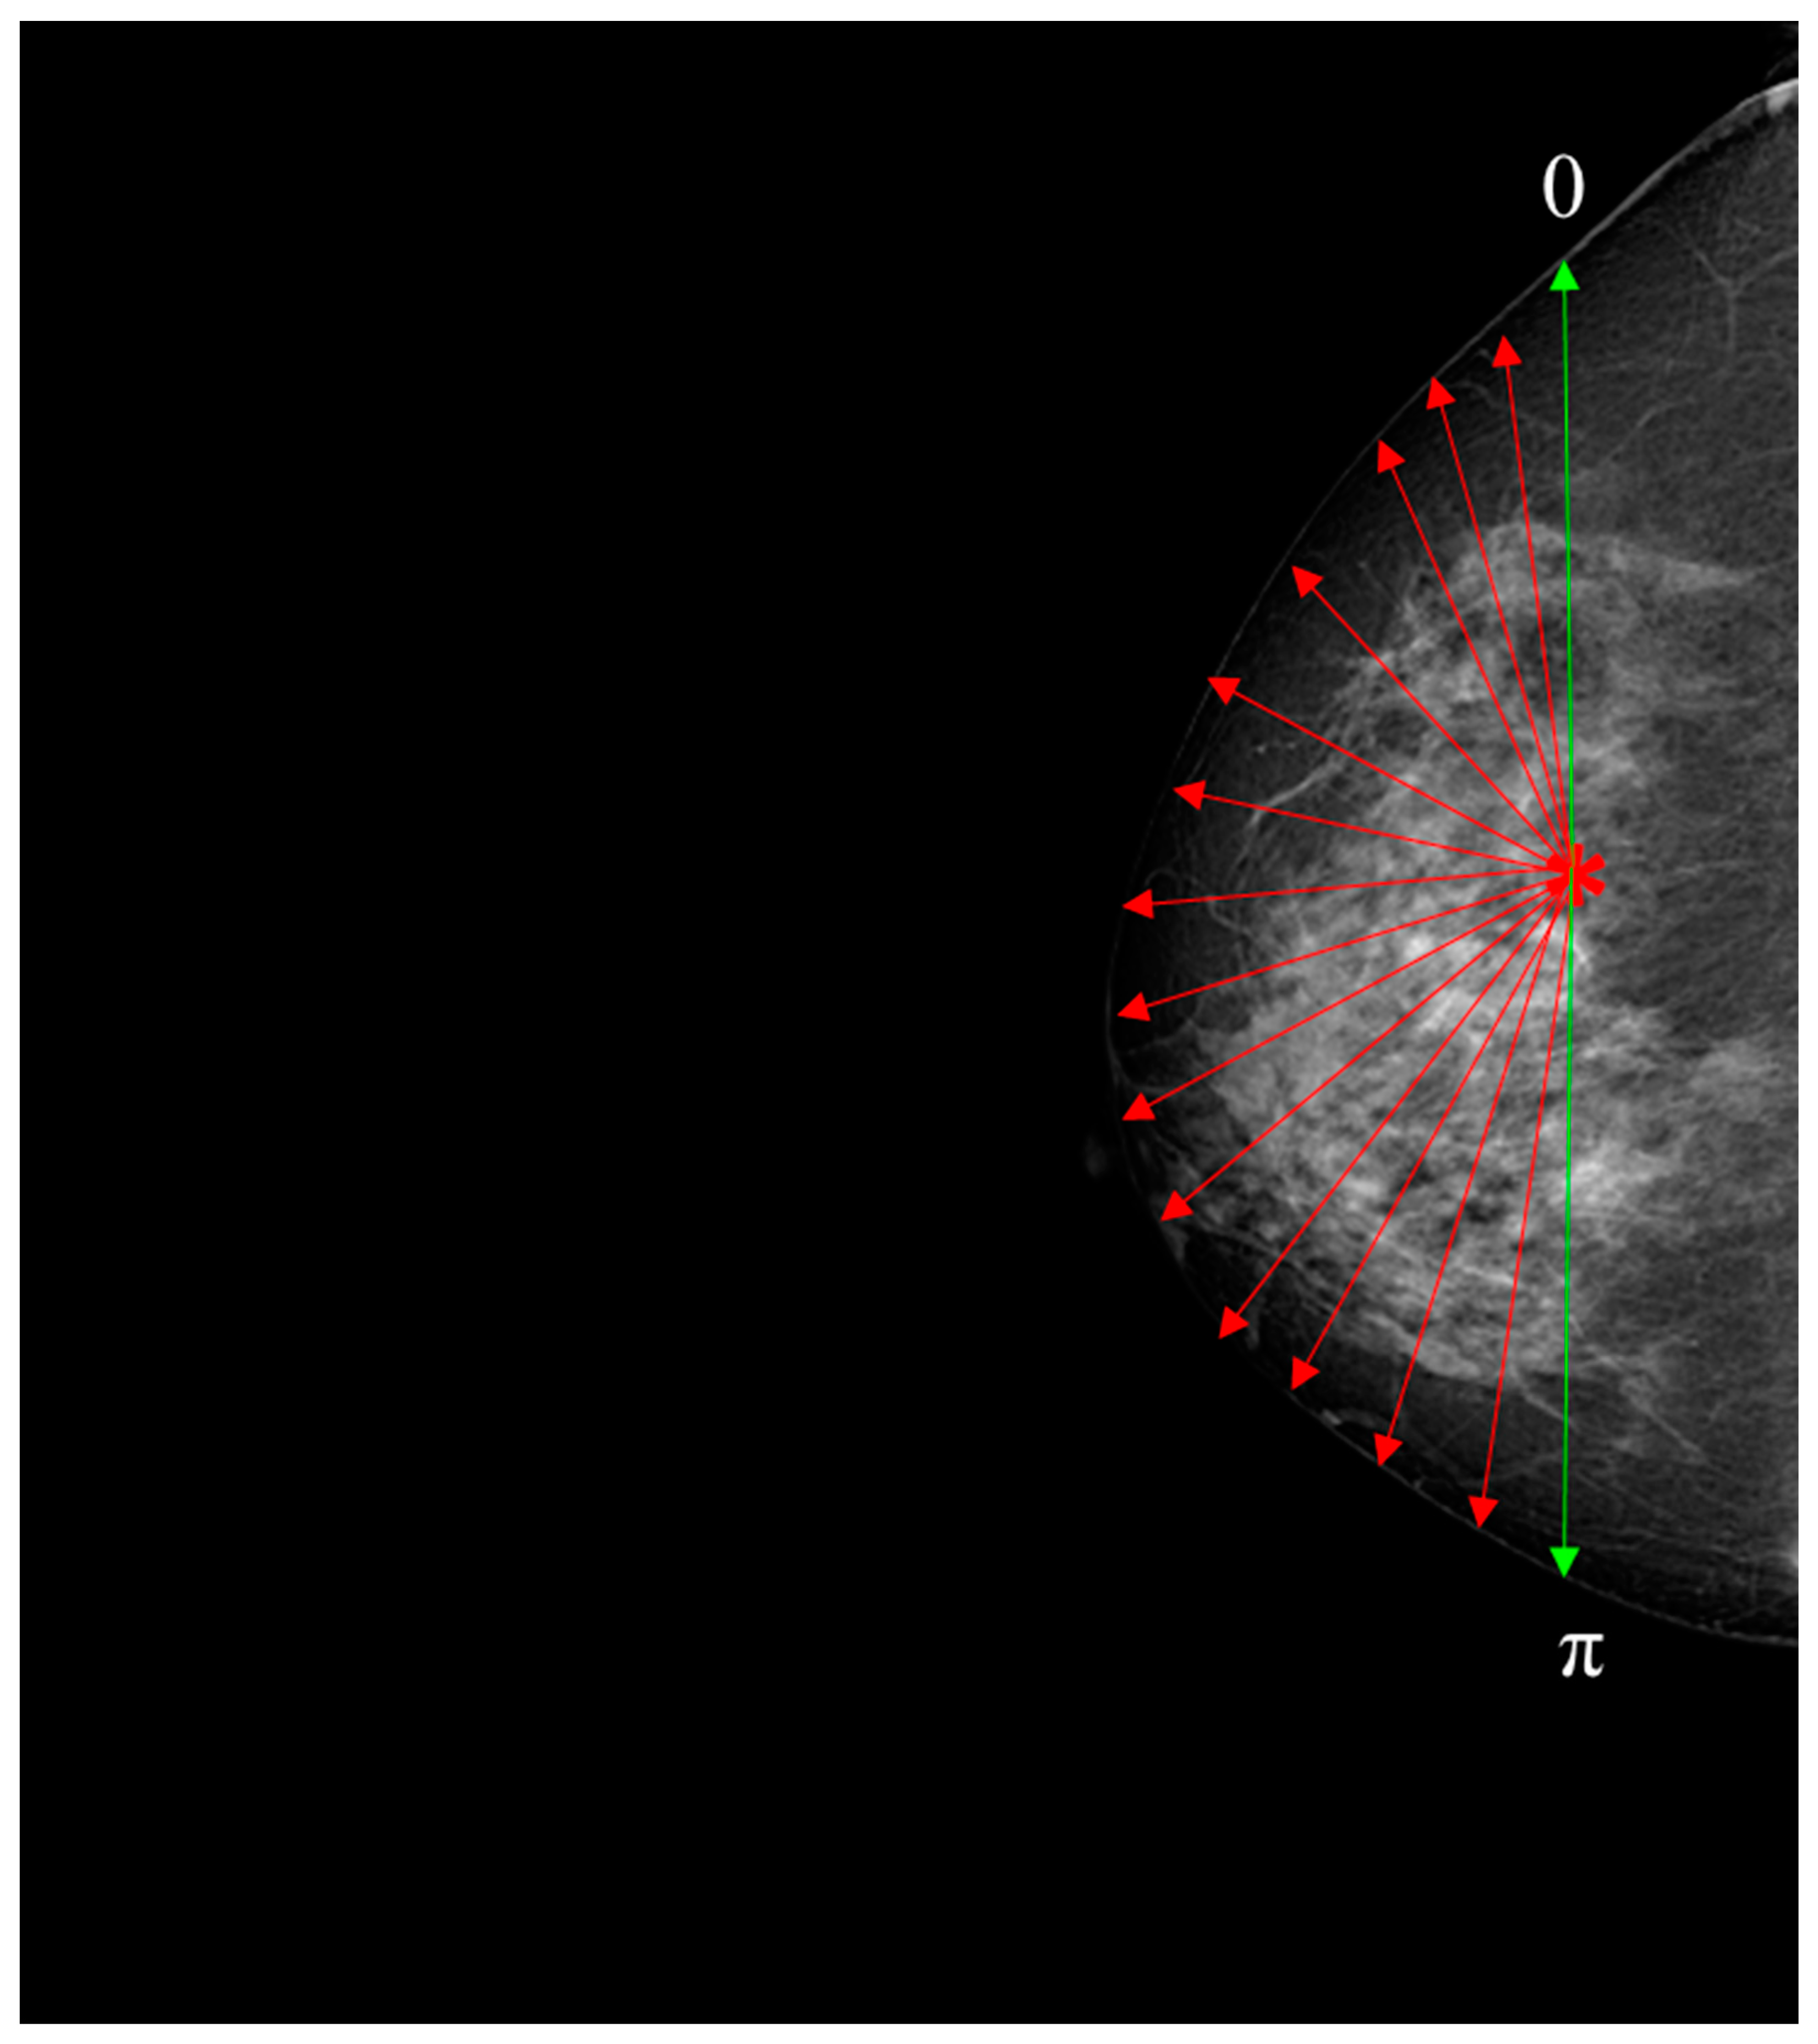

Figure 4.

This diagram serves as an illustrative representation demonstrating the process of deriving a set of distances between the centroid and the periphery of the breast. The centroid is indicated by the asterisk symbol, while the red radius is depicted as arrows extending towards the edge of the breast and the green arrows indicate the beginning and ending [0–π].

An approach to analyzing breast asymmetry is to compute a collection of radii formed between the centroid and the skin perimeter. Once the centroid is computed, the radius is retrieved based on the angle as the argument between [0, π] radians in steps of one radian, creating a distance for each orientation between the centroid and perimeter of the skin. This supports uniformity and ensures that the image is created using the outermost breast pixels. To handle variations in breast size and shape among different DICOM images, the distances between the centroid and the skin perimeter were normalized to fall within the range of [0, π]. This normalization process ensured that the spatial features used for evaluation were consistent and comparable across all images, regardless of their individual radii. By generalizing this approach to the entire dataset, we were able to effectively evaluate the morphological asymmetry in breast skin thickness and its potential significance for early breast cancer detection.